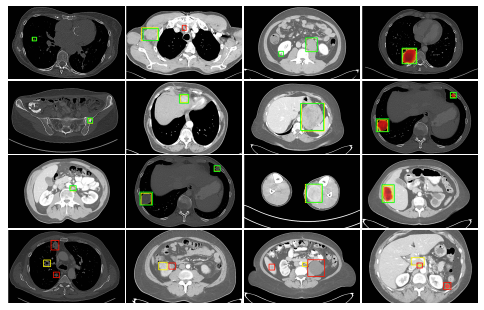

(实体肿瘤反应评估标准)标签的密集掩模的retinanet对ct病变的检测